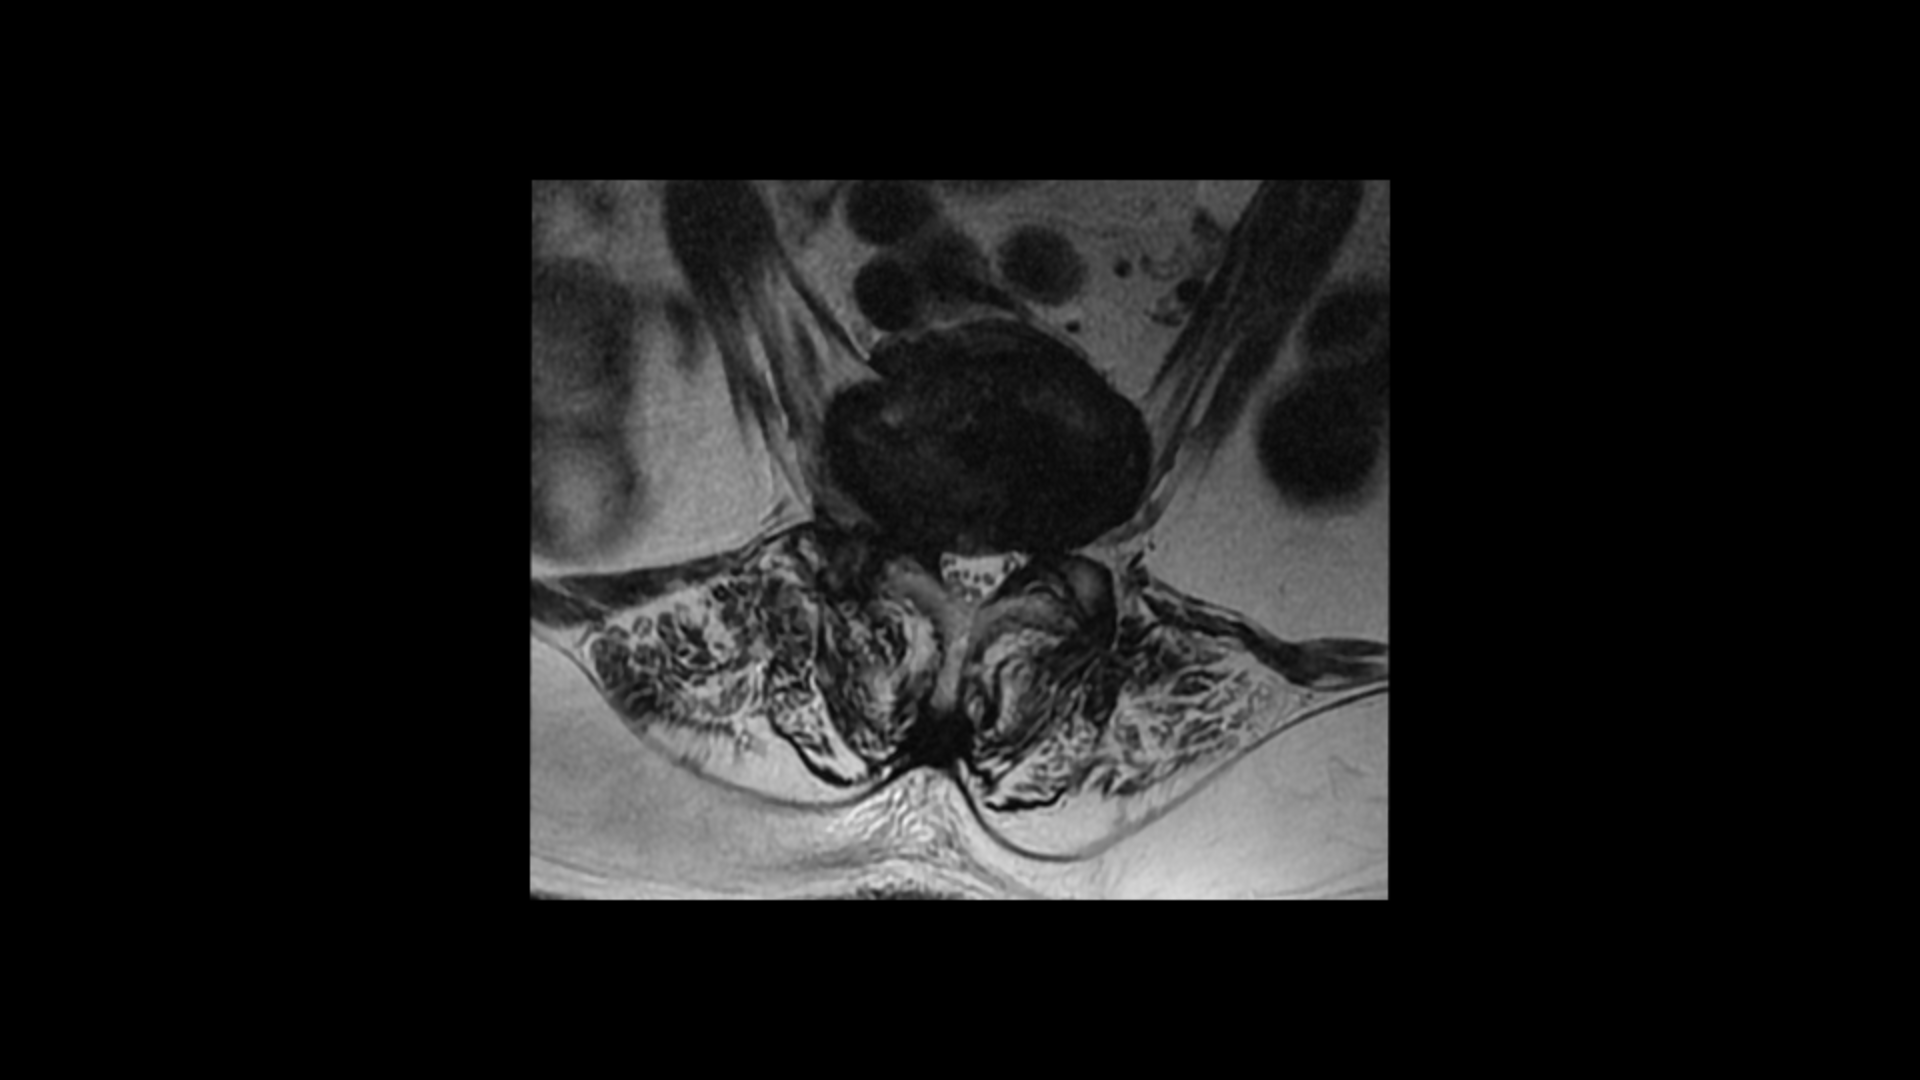

이분 MRI를 보면 보시다시피 허리의 5마디가 전부 퇴행이 진행되어 있습니다.

여러 마디 2번 3번, 4번 5번에 척추관협착이 있고

2번 3번, 4번 5번, 오른쪽 신경가지가 빠져나가는 구멍들이 다섯 마디 전부가 다 오른쪽 좁아져 있습니다.

이분의 오른쪽 엉치와 다리가 저리고 아픈 원인은 이것 때문인 걸로 보입니다.

그런데 이분은 허리도 굽으셨는데 척추근육, 특히 허리를 세워주는 기립근을 mri에서 보면 허리 다섯 마디 전체에서 기립근의 근육이 지방으로 변해서 하얗게 보이는 지방화가 심합니다.

이렇게 근육이 지방으로 심하게 변하고 기능이 떨어지면 허리를 펴기가 어렵고 허리가 아플 수 밖에 없습니다. 여기 건강한 기립근과 비교해서 보면 그 차이를 금방 알 수가 있습니다. 기립근 크기도 차이가 크고 하얗게 지방으로 변해버린 부분을 잘 보실 수 있습니다.